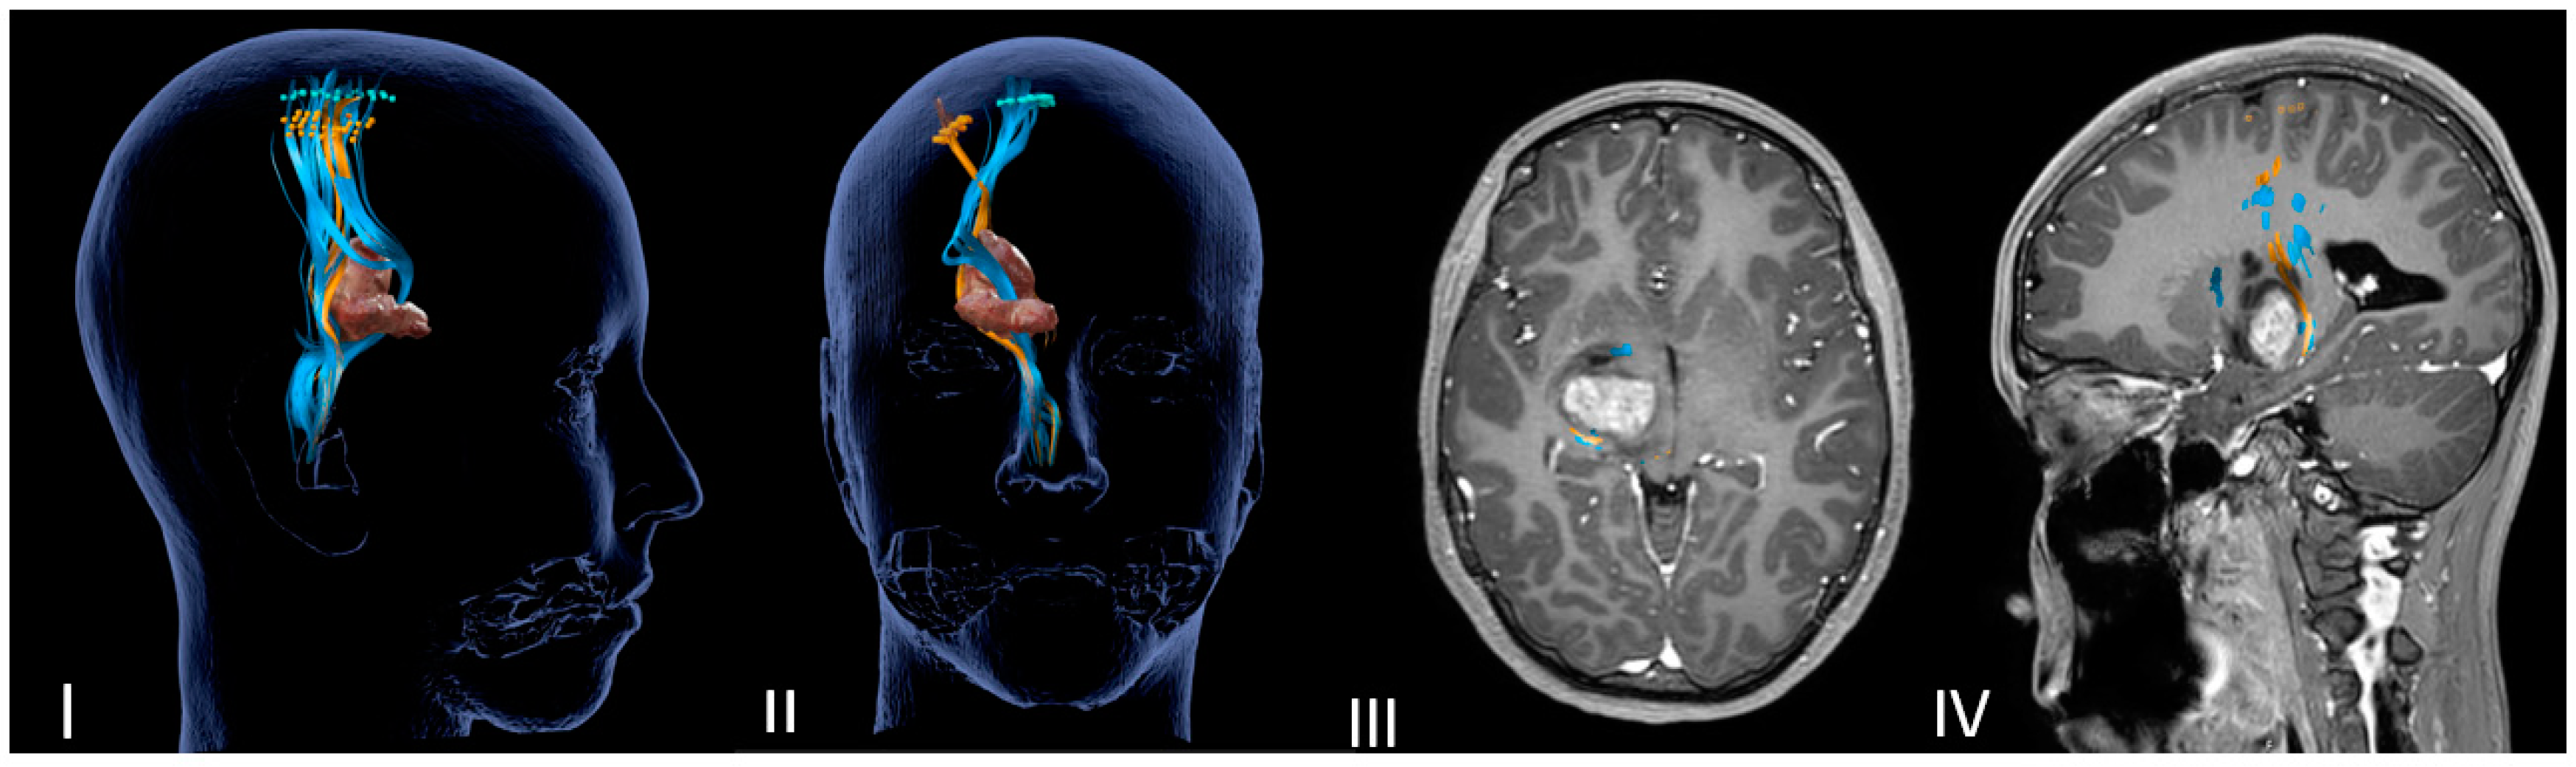

DTI-MRI CST reconstruction combined with nTMS mapping allows for an accurate tridimensional visualization of the cortical spinal bundles and helps the surgeon to choose the safer surgical corridor (Figure 1 and Figure 2).

Figure 2.

Neuronavigated transcranial magnetic stimulation pre-op study. (I,II) A 3D reconstruction of the nTMS data that shows cortical maps of the right spinal tract (CST) for the foot (blue) and hand (orange) and its relationship with the thalamopeduncular tumor of Case A. (III,IV) Brain MRI merged with nTMS data showing that the cortical spinal tract (CST) runs antero-medially respect to a right thalamopeduncular tumor.

In the most recent cases (Case A–Case B), the preoperative nTMS was performed to obtain a cortical motor mapping and the cortical spinal bundles reconstruction. The nTMS data confirmed the DTI MRI data for the motor bundles’ displacement, adding functional information about cortical and subcortical motor areas of the mouth, arms and legs (Table 3).